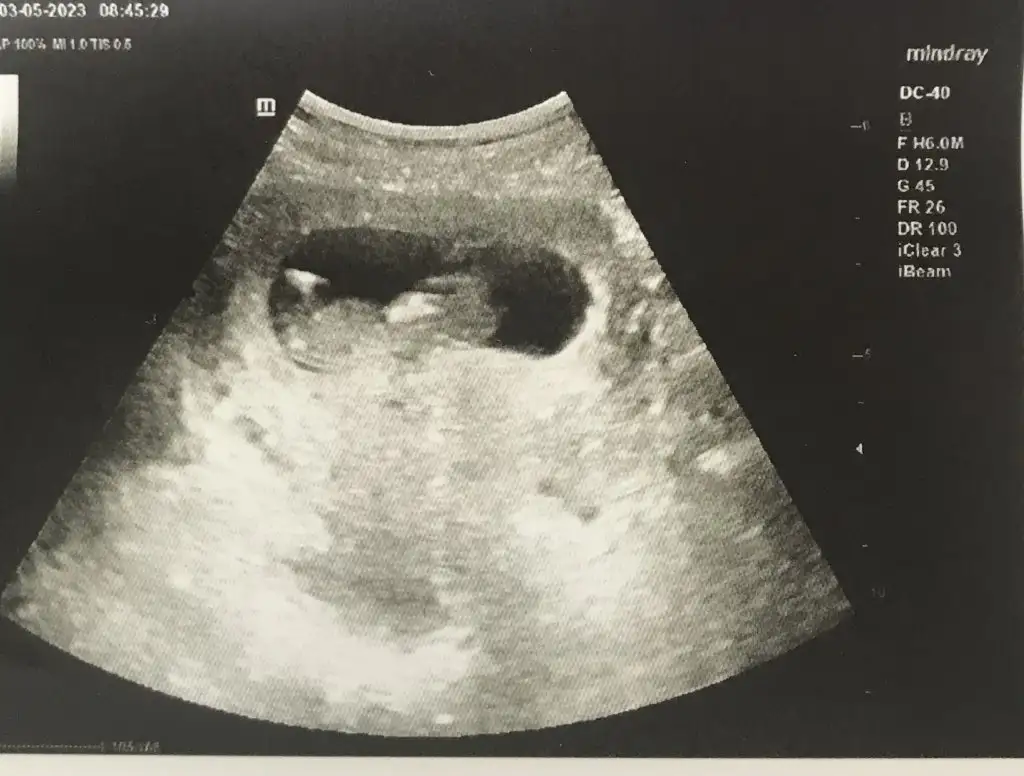

Ayyy olsun kalitesiz falan bebiş fotosu bebiş fotosudur :) Nubu görmeye çalışıyorum ama başaramıyorum :)

nubu birazdaha belli olsa iyiymis.nekadar buyumus masallah ya

Kocaman oldu bunlaaarrrr

Bence bebeği gördüğümüze dua edelimnubu birazdaha belli olsa iyiymis.nekadar buyumus masallah ya